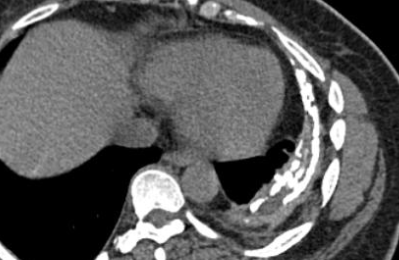

Empyème tuberculeux

- Epanchements pleuraux dans les TB primaires (Pleurite tuberculeuse), peuvent dégénérer en…

- Empyème Tuberculeux si rupture d’une cavité tuberculeuse dans la plèvre

- Épanchement pleural cloisonné

- Epaississement et irrégularité pleurales

- Calcifications pleurales

Épanchement cloisnnée par une plèvre épaisse et calcifiée